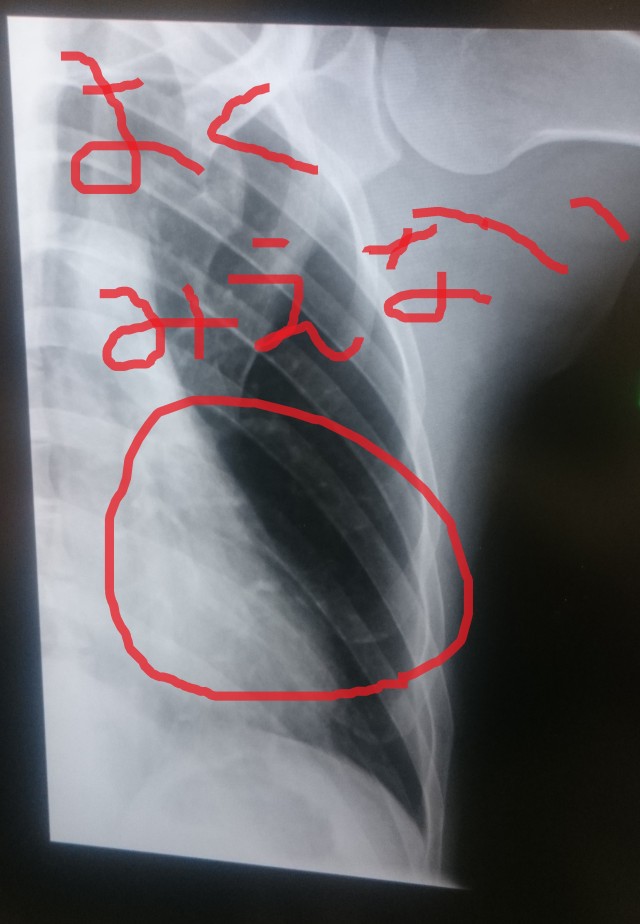

ついつい年甲斐もなくはしゃいでしまい、なんとなんと、

肋骨を折るという

雛見沢ばりの惨劇を体験をしてきました。